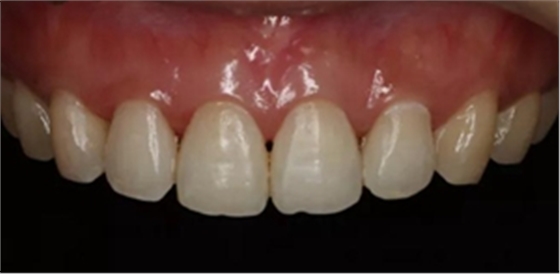

術(shù)后顯示,滲透樹脂恢復(fù)了天然牙釉質(zhì)的折光率(天然通透牙釉質(zhì)折光率1.62滲透樹脂折光率是1.52)顯的很自然,很有光澤。完全是天然牙質(zhì)的顏色。

治療前和治療后的對(duì)比,患者很高興很滿意。